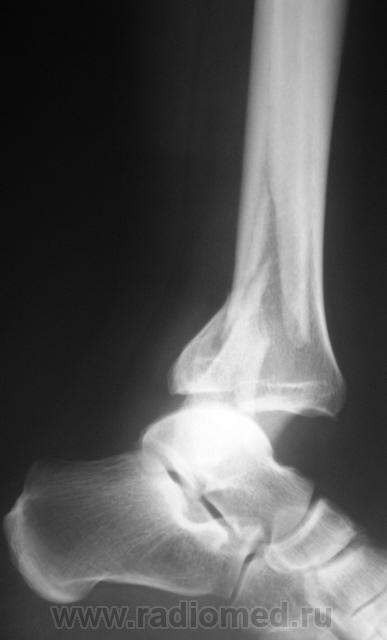

Травма. Перелом. Произведена рентгенография в стандартных проекциях в ургентном порядке.

Внутрисуставной перелом заднего края дист.эпиметафиза б/б кости или перелом "третьей лодыжки", со смещением фрагмента по ширине кзади,по длине - кверху до 5 мм и под углом, открытым кзади, с подвывихом стопы кзади, оскольчатый перелом н/3 диафиза м/б кости со смещением дистального фрагмента по ширине, по длине и угловым /открытым кзади/.

ну и еще перелом внутренней лодыжки